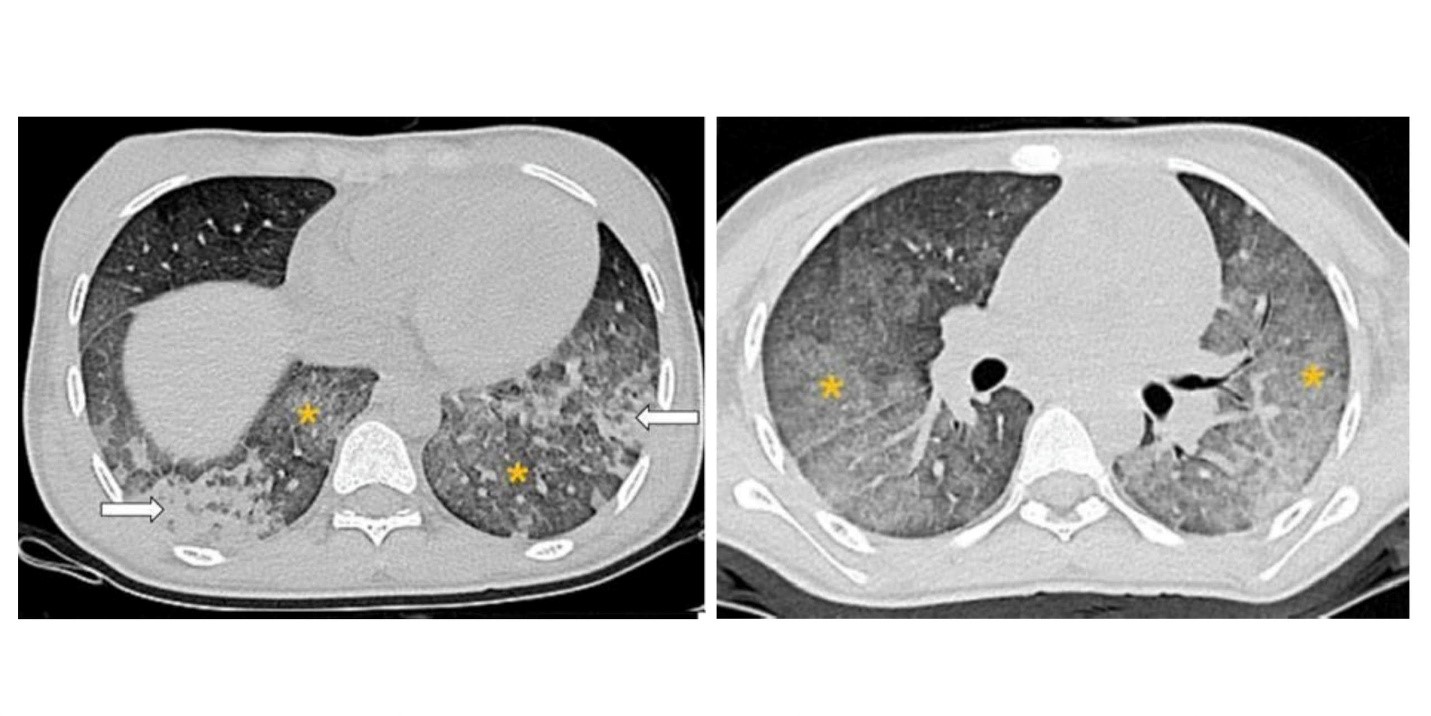

Hình ảnh chụp cắt lớp vi tính lồng ngực cho thấy hình ảnh các tổn thương gợi ý chảy máu phế nang lan tỏa

X-quang ngực có tổn thương mờ thâm nhiễm cả hai phổi, CT có hình kính mờ lan tỏa, đông đặc, dày vách phế nang phù hợp với hình ảnh của chảy máu phế nang lan tỏa.